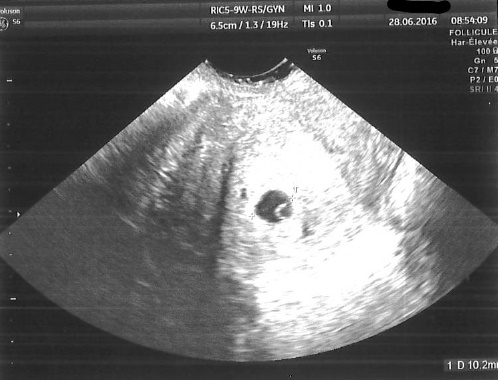

Avril 2016, Duphaston pour déclencher le cycle. Ménopur pour stimuler les follicules de J2 à J9. Ovitrelle pour favoriser la maturation le soir du J9. IAC à J10. La totale !